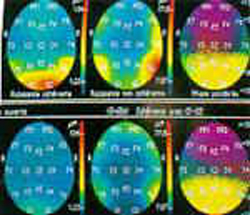

据科技日报报道,2002年,张达人教授等与美国有关大学的研究人员合作,在中国科大和美国明尼苏达大学分别完成了下围棋和下国际象棋时的脑功能核磁成像实验,对两者的脑活动情况进行了分析与比较。研究发现:下围棋时,位于大脑额叶、顶叶、枕叶、后颞叶 的多个脑区被激活,而且右侧顶叶的激活强度高于左侧,显示出右脑优势。下国际象棋时,“出力”更多的则是左侧顶叶。这提示,围棋可能更多地涉及到我们尚不理解、为人类特有的脑机制——全局性的信息统筹与加工能力。这可能正是目前的智能计算机特别需要引入的功能。